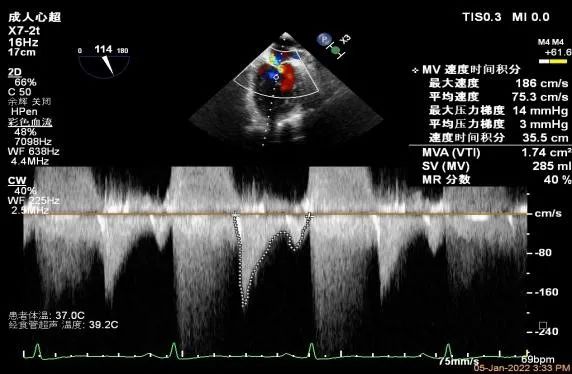

二尖瓣口平均跨瓣压差:3mmHg

第一个夹子放置侯二尖瓣口平均跨瓣压差:2mmHg

第二个夹子放置侯二尖瓣口平均跨瓣压差:3mmHg